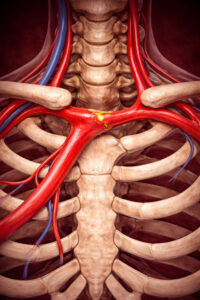

Σύνδρομο υποκλοπής υποκλειδίου αρτηρίας

Σύνδρομο υποκλοπής υποκλειδίου αρτηρίας / στένωση υποκλειδίου

Το σύνδρομο υποκλοπής υποκλειδίου αρτηρίας είναι το φαινόμενο κατά το οποίο υπάρχει ανάστροφη ροή αίματος (η ροή του αίματος είναι αντίθετη από τη φυσιολογική της φορά) σε έναν από τους αρτηριακούς κλάδους της υποκλειδίου αρτηρίας σαν αποτέλεσμα μιας αιμοδυναμικά σημαντικής ομόπλευρης (της ίδιας πλευράς) στένωσης στο εγγύς τμήμα της υποκλειδίου αρτηρίας.